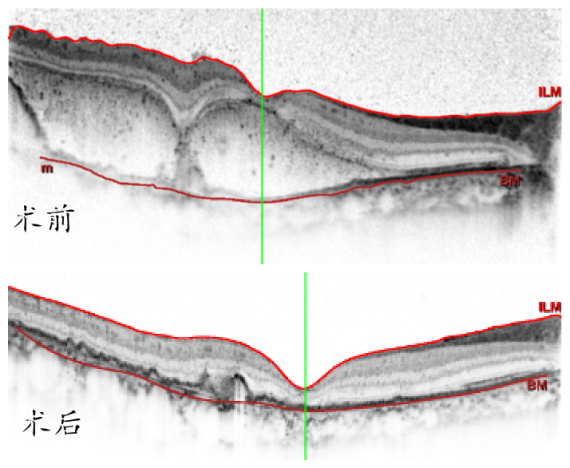

胡志翔医师介绍,温医大眼视光医院吴荣瀚教授早在 2010 年开展了针对